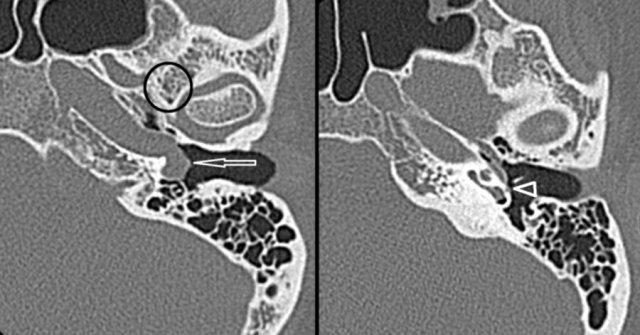

Đường đi bất thường của động mạch cảnh trong (ICA) hoặc động mạch bàn đạp

Đường đi bất thường của động mạch cảnh trong và sự tồn tại dai dẳng của động mạch bàn đạp là các biến thể bẩm sinh cần được nhận biết trên các phương tiện chẩn đoán hình ảnh.

Đường đi bất thường của động mạch cảnh trong tai giữa có thể bắt chước hình ảnh khối mô mềm hoặc u cận hạch khi soi tai.

Bên trái là hình ảnh đường đi bất thường của động mạch cảnh trong (mũi tên) và sự tồn tại dai dẳng của động mạch bàn đạp (đầu mũi tên) trên CT lát mỏng.

Lưu ý sự vắng mặt của lỗ gai (encircled).